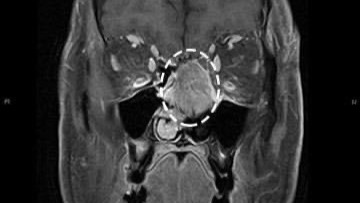

Sheridan was first diagnosed with a rare and aggressive cancer called Sinonasal Undifferentiated Carcinoma (S.N.U.C.) in October 2018. It's cancer originating in the epithelial layer of the nasal cavity or paranasal sinuses. She had just gotten glasses for the first time and started getting headaches. Sheridan thought the new glasses caused the headaches and growing bump. Several visits to the doctor and testing told her she had a brain tumor. The tumor was growing between her eyes and was quite noticeable.

Unfortunately, this time (2021 - current), cancer returned. Sheridan has been in her THIRD fight for the last year or so. She's been bedridden and sick most of this time. She was getting weekly chemo, but she got too weak and had to take a two-month break over the summer to gain weight. She was finally able to eat and gained nearly 20 pounds. The tumor is pressing on her left eye area, making her vision blurry. It's not safe for her to drive her son to school anymore. The tumor is growing.

An MRI is ordered, and hopefully, another surgery appointment is set.